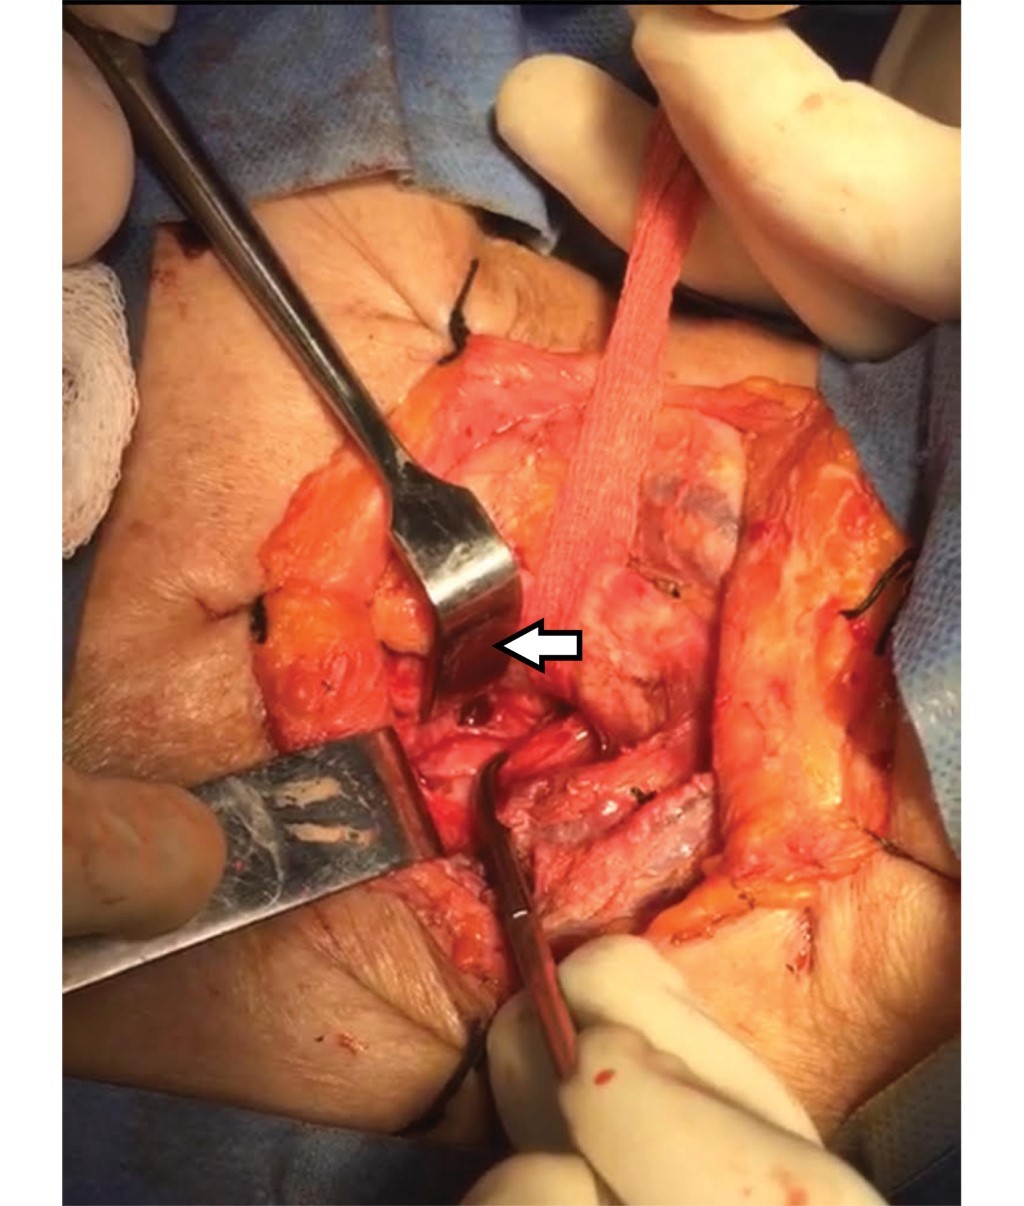

Femenino de 69 años. Ingresa a la Unidad de Terapia Intensiva (UTI) con diagnóstico de neumonía COVID-19, SDRA severo por Berlín con PaO2/FiO2 80 mmHg, pulsioximetría 92%, en ventilación mecánica invasiva (VMI) presión control 17 cmH2O, FiO2 60%, PEEP 12 cmH2O y frecuencia respiratoria 21/minuto. Al día 12 de VMI se realiza TP en la UTI con técnica de Ciaglia Blue Rhino.1 Se realiza incisión transversal de 2 cm a nivel del segundo anillo traqueal y punción entre el segundo y tercer anillo traqueal. A la aspiración se obtiene líquido citrino, por lo que se retira aguja y en una segunda punción se logra acceso efectivo. Se introduce cánula de traqueostomía de 8.5 mm y es conectada a la VMI; al momento presenta broncoespasmo tratado con broncodilatador y se realiza cambio de dispositivo a bolsa válvula mascarilla con reservorio; presenta resistencia a la ventilación con evidencia de enfisema subcutáneo masivo en tórax e hipoxemia por neumotórax a tensión bilateral; evoluciona a bradicardia y finalmente asistolia, se inician maniobras de reanimación, se realiza descompresión bilateral con aguja Punzocat no. 14, se asegura vía aérea con cánula orotraqueal de 8.5 mm al primer intento. Se logra retorno a la circulación espontánea con taquicardia sinusal e hipotensión, se colocan sondas endopleurales bilaterales y se procede a realizar fasciotomías pectorales para drenaje de enfisema subcutáneo; se observa en cámara de succión de Pleur-Evac® fuga aérea bilateral. Se recupera estabilidad hemodinámica a las 4 horas del evento y se realiza tomografía de tórax (Figura 1). La broncoscopia muestra laceración posterior de la tráquea (Figura 2). Por endoscopia se descarta lesión esofágica. El tratamiento inicial es conservador mediante ferulización traqueal durante 15 días. La broncoscopia de control muestra limitación de la perforación y tejido epitelizado; se decide cierre de lesión traqueal con parche de músculo esternohioideo izquierdo, se verifica aerostasia sin observar fuga (Figura 3). Se realiza traqueostomía a nivel de segundo y tercer anillo traqueal, y se coloca cánula de 7 mm Bivona® (Smiths Medical, Minnesota, EEUU), la rama distal queda pasando la perforación, se verifica aerostasia y hemostasia, se coloca drenaje Jackson Pratt® 10 mm (Bard, Covington GA USA) a lecho quirúrgico, con evolución radiográfica que demuestra expansión pulmonar, sin enfisema subcutáneo ni neumomediastino (Figura 4). Al quinto día del procedimiento quirúrgico cursó con broncoespasmo severo y obstrucción traqueal, presenta parada cardiaca sin lograr retorno espontáneo de la circulación.

Figura 2

Figura 4